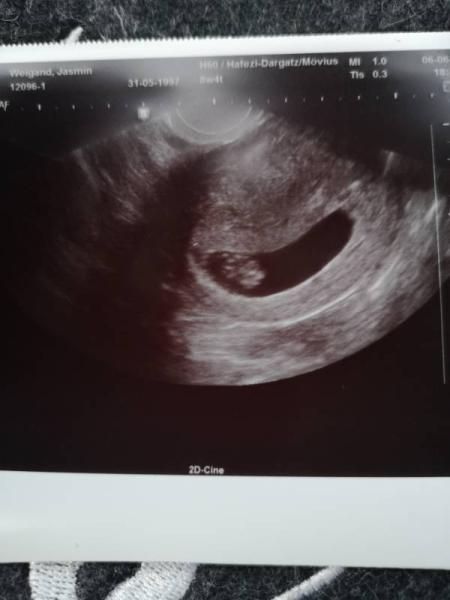

Hallo, Ich hatte heute meinen zweiten Frauenarzt Termin, bin heute 8+4, das Würmchen ist 1,5 cm groß, Herzchen hat kräftig geschlagen und ich konnte arme und Beine sehen Leider habe ich immernoch ein wenig mit der Blasenentzündung zu kämpfen, aber zum Glück sind die starken Nierenschmerzen besser, Entzündungswerte sind allerdings noch ein bisschen erhöht, außerdem ist mein Blutdruck etwas zu hoch, den soll ich jetzt selber jeden Tag Messe und notieren und wenn er einen gewissen Wert übersteigt muss ich vorbeikommen aber bin guter Dinge

Bild zu 2. US Termin :) - Forum für Januar - Mamis